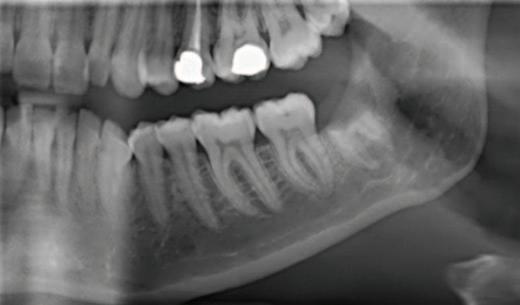

A partially erupted lower le third molar with a prominent operculum was noted during the intraoral examination. The orthopantomogram taken suggested a close relationship of the tooth with the IAN due to a relative rarefaction associated with the distal root, indicating proximity of the nerve canal with little or no bone interposition (Figure 1). Caries was also noted occlusally on the lower le second molar and a deep restoration on the upper le first molar. Following the exclusion

FIGURE 1: Orthopantomogram showing the partially erupted lower left third molar.